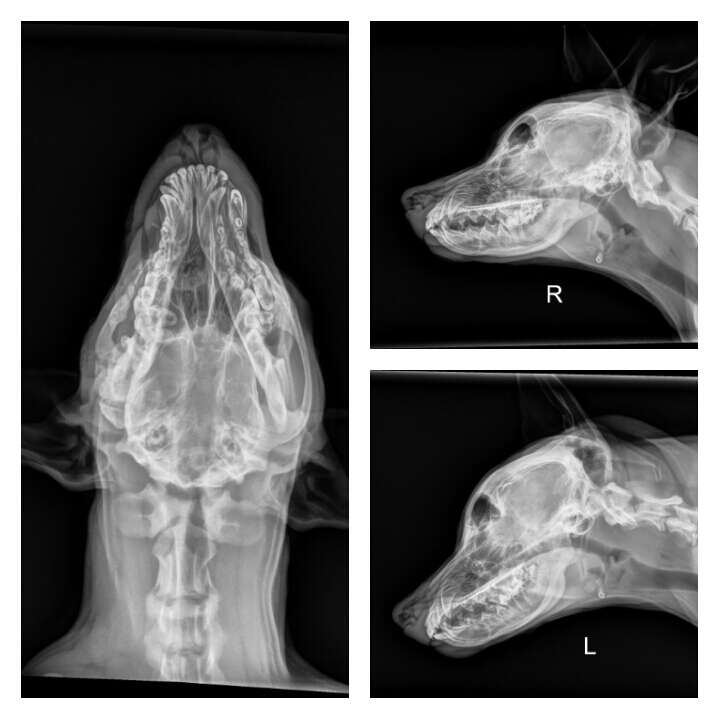

Cuando Squish, originalmente llamado Zar en el refugio, llegó a VCA Great Lakes Veterinary Specialists para una segunda opinión antes de la eutanasia, no podía abrir la mandíbula y estaba perdiendo peso. El veterinario del refugio decidió llevarlo a VCA Great Lakes Veterinary Specialists para obtener una segunda opinión antes de la eutanasia. Fue evaluado por un equipo compuesto por especialistas, incluidos la Dra. Eileen Heldmann, la Dra. Katie Frantz y la Dra. Emily Conway. Se tomaron radiografías y al dulce cachorro con la cara torcida se le realizó una tomografía computarizada. Los resultados fueron impactantes.

Squish tenía fracturas significativas en el cráneo y la mandíbula superior derecha. Aunque su ojo derecho estaba intacto, se había hundido detrás de los huesos aplastados que debían soportar el ojo. Tenía una cantidad masiva de tejido cicatricial alrededor de su mandíbula. El tejido cicatricial había evitado que su mandíbula creciera junto con su cuerpo, lo que hacía cada vez más difícil abrir la boca.

Las radiografías revelaron múltiples fracturas y tejido cicatricial en el lado derecho del rostro de Squish. El tejido cicatricial impedía que Squish abriera la boca para comer.

Los tres especialistas se estremecieron al darse cuenta de que, debido a la naturaleza específica de sus lesiones, Squish había sufrido un fuerte golpe directamente en la cabeza. No tenía ningún otro traumatismo en su cuerpo, lo que llevó a los especialistas a concluir que sus lesiones fueron causadas intencionalmente, por alguien que usó un objeto contra su cabeza.